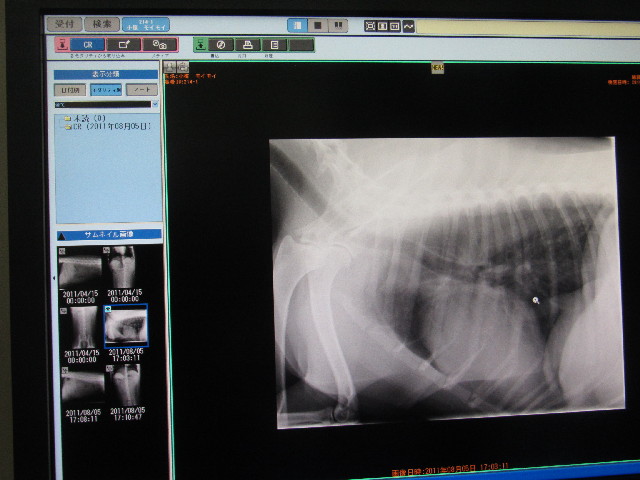

レントゲンも撮ってもらいました。

●気管が少し石灰化してて、(首の部分の左側が少し白くなっているでしょ?)、先生は(年齢にしては)石灰化するのが早いなぁ.....とおっしゃっていました。

spleenと書いてあるところが脾臓

kid(kidney)と書いてあるところが腎臓

どこも異常はなく、前回のレントゲンとも比較しましたが今日の方が腸にガスが多く溜まっているくらいで問題はなし!(^^)!